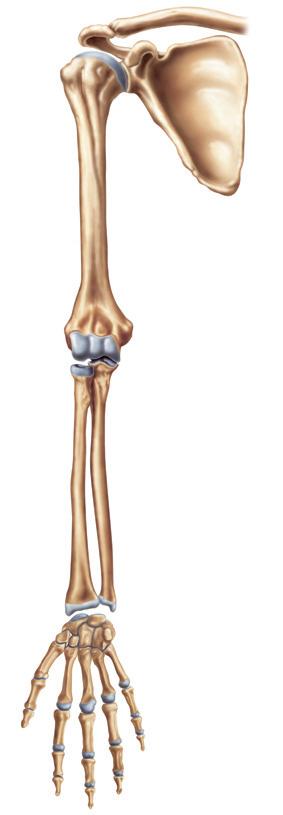

Abb. 2: Ertaste und benenne Knochen in deinem Körper!

Vergleiche Arm- und Beinskelett! Was ist ähnlich und wo gibt es Unterschiede?

Alle Knochen deines Körpers bilden zusammen das Skelett . Das menschliche Skelett besteht aus mehr als 200 Knochen und Knorpeln Knorpel sind elastisch und verhindern, dass Knochen aneinanderreiben.

Unsere Arme und Beine nennt man Gliedmaßen. Sie sind die beweglichsten Teile unseres Körpers. Die Arme sind mit dem Rumpf durch den Schultergürtel verbunden.

Er besteht aus den beiden Schulterblättern und den Schlüsselbeinen. Die Beine sind durch den Beckengürtel mit dem Rumpf verbunden.